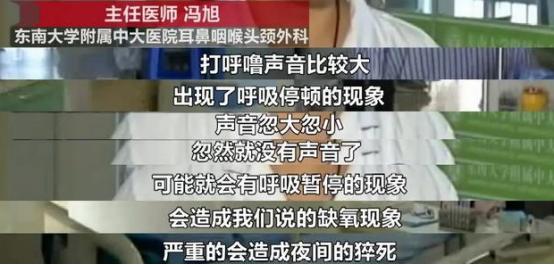

这种情况,叫“病理性打呼”。这是一种“恶性打呼”,呼声大、不规律

有时打着突然停顿,一口气上不来!

它就是上面说的,“睡眠呼吸暂停综合征”。

得了这种病,最直接的致死因素就是:由于呼吸暂停,造成心脏缺氧,诱发心肌梗死。 我们的血液会带着氧气,输送到各器官使用。人体正常的“血氧饱和度”,应该维持在95%以上。

我们的血液会带着氧气,输送到各器官使用。人体正常的“血氧饱和度”,应该维持在95%以上。但医生监控显示,当患者睡眠呼吸暂停10秒后,血氧浓度就从95%下滑到88%,处在安全线之下!

心肌细胞等不来血氧使用,就可能导致心力衰竭。如果呼吸暂停超过3分钟,容易在睡梦中猝死。